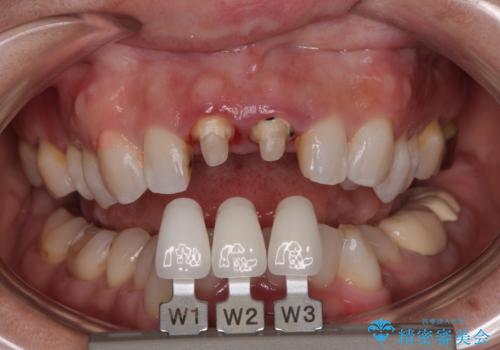

- 前歯の色が黄色くなって気になるとのことで来院された患者様です。

約20年前に前歯の根管治療を行い、保険の被せものを入れたとのことです。

拡大鏡視野下で、被せもの、金属の土台、虫歯を除去し、ファイバーの土台(ファイバーコア)をたてて、オールセラミッククラウンに適した形に整えました。

患者様のご希望で周りの歯も白くしたいとのことでオフィスホワイトニング、ホームホワイトニングで色の調整を行い、色味が落ち着いてから、歯と歯茎の間に圧排糸と呼ばれる糸を入れてシリコーン印象を行いました。